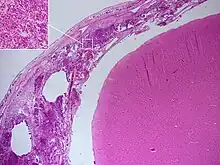

Histopathology of bacterial meningitis: autopsy of a person with pneumococcal meningitis showing inflammatory infiltrates of the pia mater consisting of neutrophil granulocytes (inset, higher magnification).

Meningitis can be diagnosed after death has occurred. The findings from a post mortem are usually a widespread inflammation of the pia mater and arachnoid layers of the meninges. Neutrophil granulocytes tend to have migrated to the cerebrospinal fluid and the base of the brain, along with cranial nerves and the spinal cord, may be surrounded with pus – as may the meningeal vessels.[52]